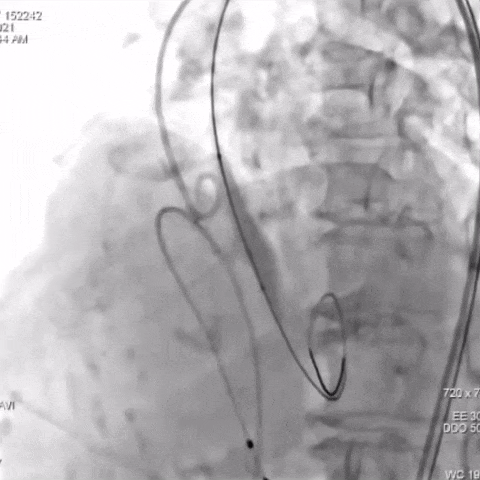

TaurusNXT植入过程:

主动脉瓣根部造影

球囊预扩

瓣膜第一次展开与回收

瓣膜再次定位与展开

瓣膜稳定释放